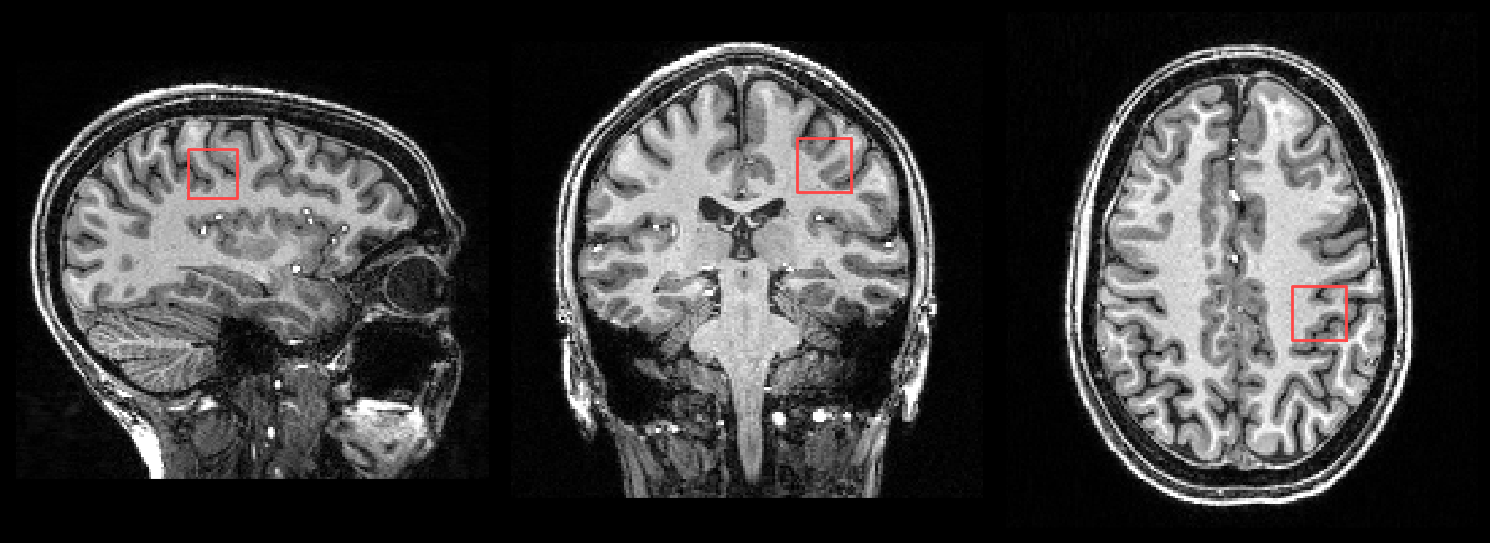

When a T1 image is provided, the SVS voxel location is also shown both the HTML reports and in a PNG file (voxel_location.png):